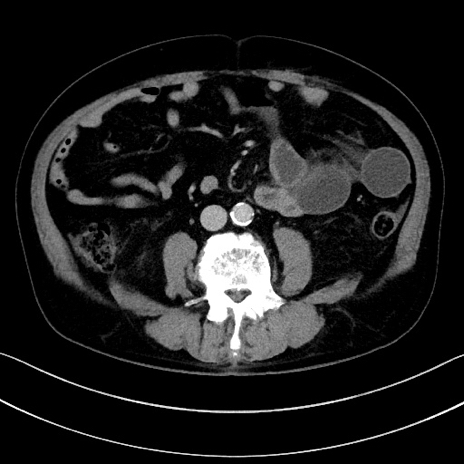

症例15(横断像)

【症例】70歳代男性

【主訴】腹痛

【現病歴】今朝から腹痛あり。全体的に痛い。特に左上の方。排ガスが今日はない。冷や汗が出る。

【既往歴】直腸癌術後

【身体所見】左側腹部〜上腹部に圧痛あり。腹膜刺激症状明らかなではない。軽度反跳痛。左下腹部に術後瘢痕あり。

【データ】WBC 7700、CRP 0.02